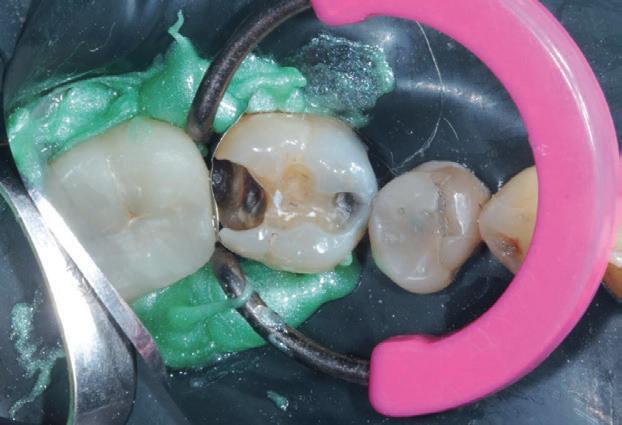

Un pacient caucazian în vârstă de 77 ani s-a prezentat la clinica autorului după cinci ani în care nu a fost la niciun control stomatologic. Examinarea clinică a arătat o pierdere semnificativă de os, parodontită cronică și multiple edentații care au destabilizat ocluzia. Pacientul a raportat sensibilitate la rece la nivelul primului molar drept inferior nr. 46, în special la ingerarea de lichide reci. Radiografia periapicală a confirmat constatările examenului clinic; în

plus, s-a detectat și prezența unei carii radiculare la nivelul rădăcinii distale a aceluiași molar, cu răspuns pozitiv la testul de sensibilitate (fig. 1-2).

Planul de tratament a început cu accent pe restabilirea sănătății parodontale. Într-o ședință ulterioară, odată cu îmbunătățirea stării parodonțiului, s-a efectuat restaurarea molarului nr. 46. Sub anestezie la Spina Spix pe partea dreaptă și

izolarea cu digă de cauciuc, restaurarea din amalgam a fost îndepărtată complet și s-a obținut accesul la cavitatea carioasă (fig. 3-5). În ciuda proximității față de țesutul pulpar, nu a avut loc nicio expunere, iar cavitatea de clasa a II-a a fost restaurată complet cu Biodentine™ (fig. 6-8).

Figurile:

6. Biodentine™ aplicat prin procedura

Bio Bulk-Fill. 7. Situația clinică după 12 minute și îndepărtarea matricii.

8. Situația clinică după îndepărtarea digii de cauciuc. 9. Radiografia de control la 2 luni postoperator.